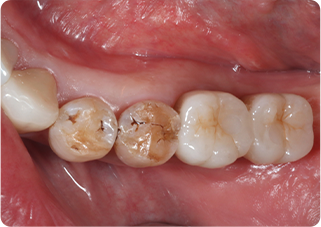

セラミックオーバーレイ症例②

術前

ラバーダム防湿

技工物

仮歯

| 主訴 | 左下奥歯が噛むと痛い時がある |

|---|---|

| 治療期間/回数 | 2週間、2回 |

| 価格(税込) | 77,000円(税込) |

| リスク・副作用 | セラミックの破損、一時的な知覚過敏が生じる場合がある |

| ポイント | 歯科技工士により、奥歯であっても周囲の歯に自然に馴染む色合いで精密なセラミックを作製。またセラミック装着時にラバーダム防湿を行うことで、詰め物の接着効果を最大限発揮できるようにした。 |